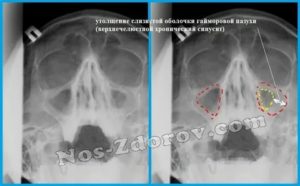

- Рентгенография. Самый популярный метод исследования околоносового пространства, позволяющий определить полноту воспалительного процесса, количество скопившейся в пазухах слизи, присутствие в носу полипов. ,

- рентгенография (снимок помогает рассмотреть назальные полипы);

- рентгенография;